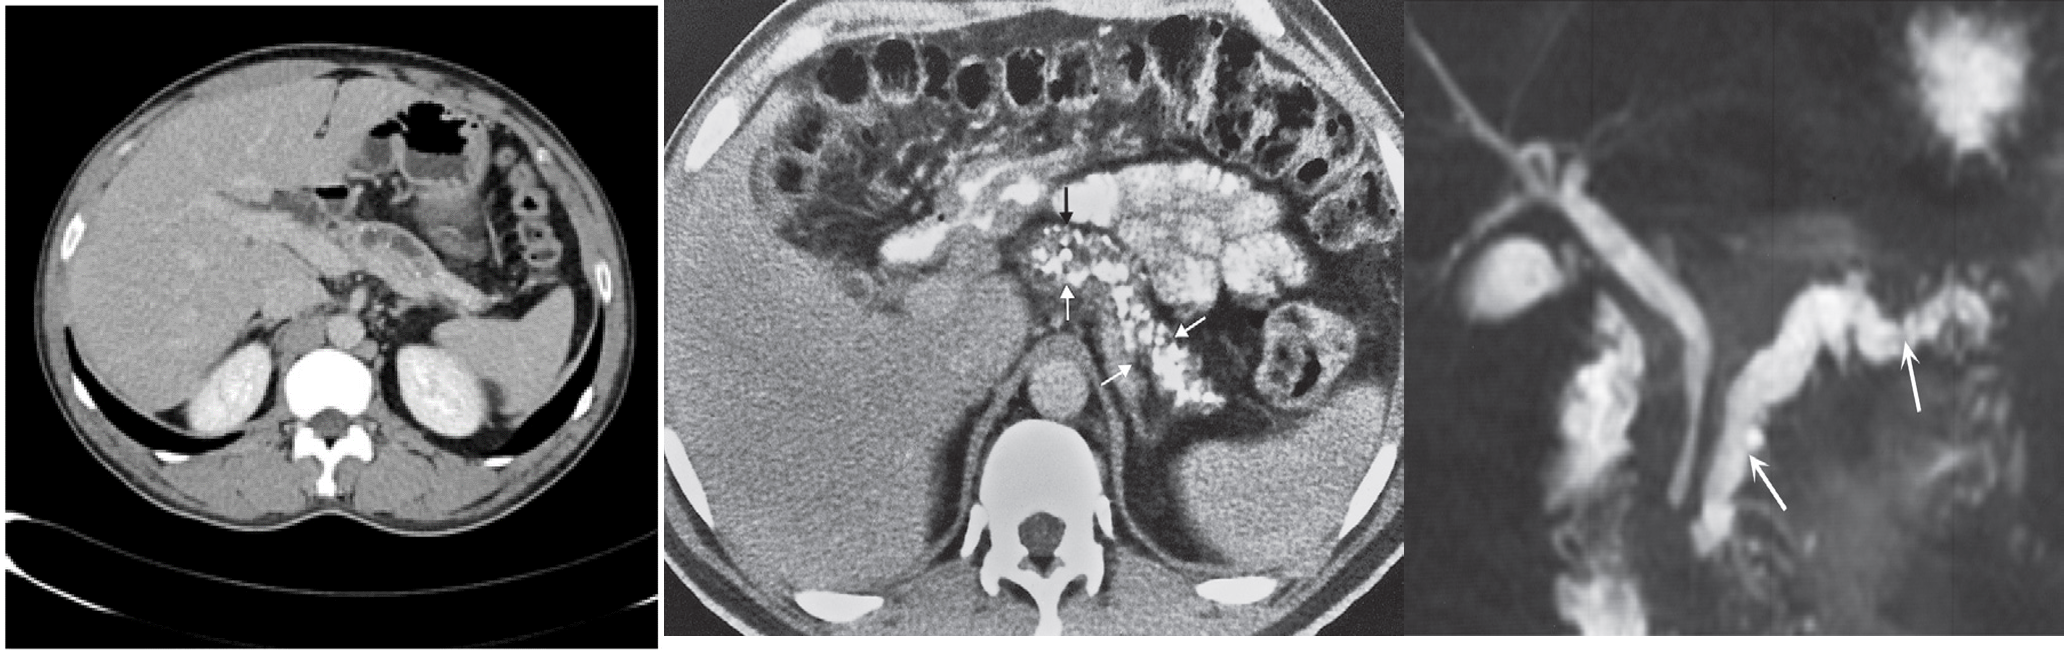

Chronic pancreatitis results in calcifications; calcifications in chronic pancreatitis are often recognizable on plain films and ultrasound, but are particularly obvious at CT. - The pancreas may atrophy focally or generally.

(A) Within the body of pancreas, the main pancreatic duct shows alternating segments of dilatation and stenosis. There is atrophy of the pancreatic parenchyma, and a few punctate calcifications are seen.

The CT features are compatible with a diagnosis of chronic pancreatitis.

(B) CT scan showing numerous small areas of calcification within the pancreas (arrows).

(C) MRCP showing a normal biliary duct system but irregular dilatation of the pancreatic duct (arrows).